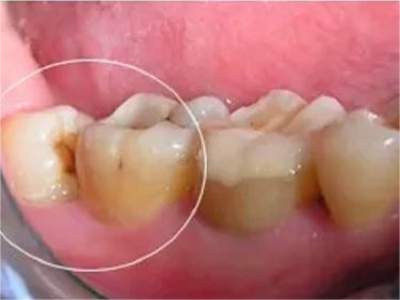

阻生牙可反复引起冠周炎,或引起邻牙牙根吸收和破坏,位置不正,不能完全萌出,好发部位是上、下颌第三磨牙。

对于阻生牙的处置需要首先明确阻生牙齿发育情况是否正常,对于由于早期外伤或其他原因造成发育异常,如牙根弯曲、短根等情况的阻生牙,还应根据患者的综合情况,决定牙齿是否保留。